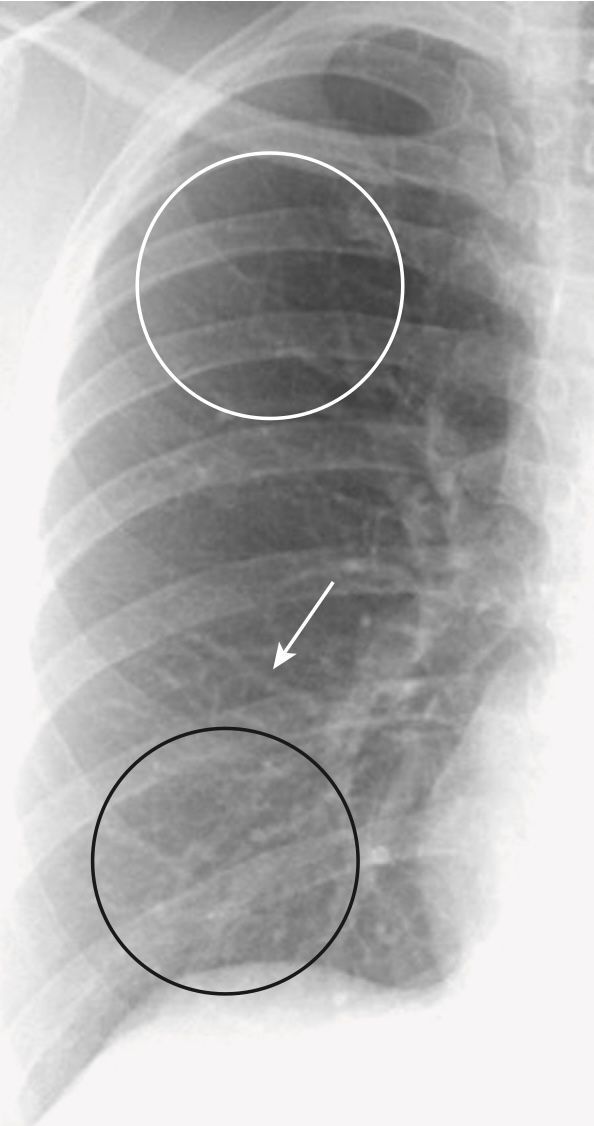

- Hình 1 hiển thị một số đặc điểm giải phẫu bình thường có thể nhìn thấy trên phim chụp X quang ngực thẳng.

- Hầu như tất cả “đường trắng” mà bạn nhìn thấy trong phổi trên phim chụp X quang ngực đều là mạch máu. Các mạch máu có đặc trưng phân nhánh và nhỏ dần từ rốn phổi trung tâm đến các rìa ngoại vi của phổi. Trên phim chụp X quang thông thường, không thể phân biệt chính xác giữa động mạch phổi và tĩnh mạch phổi.

- Ở tư thế thẳng đứng, lưu lượng máu đến đáy phổi thường lớn hơn lưu lượng đến các đỉnh phổi vì tác dụng của trọng lực. Do đó kích thước của các mạch máu ở đáy phổi thường lớn hơn kích thước của các mạch máu ở đỉnh phổi.

- Thông thường, các mạch máu phân nhánh và nhỏ dần từ trung tâm (rốn phổi) đến ngoại vi (gần thành ngực) (Hình 2).

- Trên phim chụp X quang ngực thẳng, các ngách này dễ dàng nhìn thấy nhất ở rìa ngoài của phổi gọi là ngách sườn hoành bên (còn được gọi là góc sườn hoành bên) và trên phim chụp X quang nghiêng là ngách sườn hoành sau (còn được gọi là góc sườn hoành sau) (xem Hình 1 và 3).